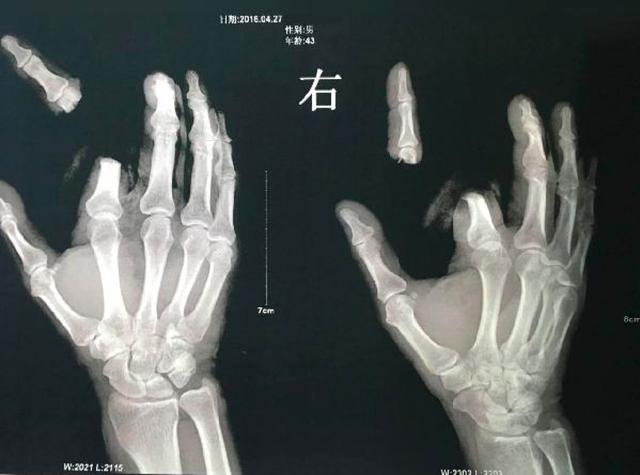

隐翅虫毒液可轻易致人死亡?

在湖南常德,曾有一名男子不小心将一只隐翅虫捏死,因皮肤沾上了少许毒液,随后开始出现水泡。因听信隐翅虫的毒液可致人死亡的谣传,该男子在情急之下竟拿起菜刀,将自己的右手食指砍下。家人将其送医后,手指才侥幸接回。

断指男子X光照片